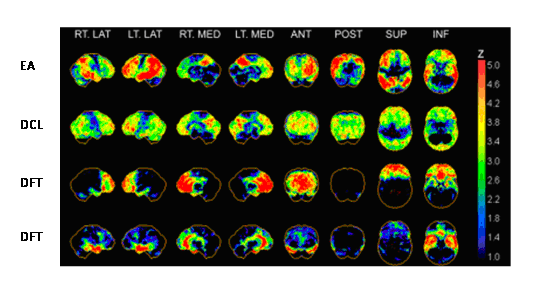

Aplicaciones del PET en el estudio de las demencias

Rol del PET-CT en pacientes con Ataxia Cerebelosa